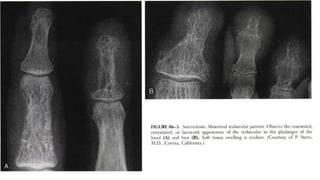

 Highly probable sarcoid arthritis includes the typical features of the

trabecular pattern, osteolysis, cyst formation, and punched-out lesions

 Highly probablesarcoid arthritis includes the typical features of the trabecular pattern, osteolysis, cyst formation, and punched-out lesions

Subcutaneous nodules. Observethe prominent soft tissue nodules in the second and third digits, with acro-osteolysis of the terminal tufts.